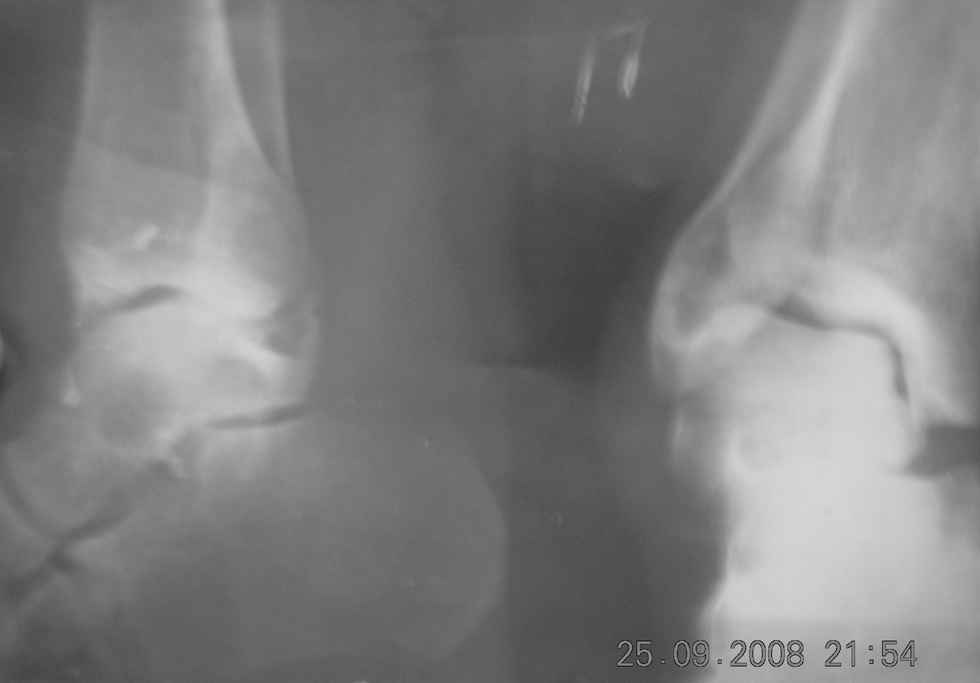

Прислано latif 25 Сентябрь 2008, 21:25

из Бухарская областная больница

Bolnoy tri mesatsa tomu nazad padvernul nogu lechilsya v SRB

nalojen gips, snyat cherez tri mesatsa posle snyatiy gipsa atmechayetsya varusnaya defarmatsiya stapi boli pri nagruzke konechnosti prashu pomoch v plane i taktiki lecheniya.